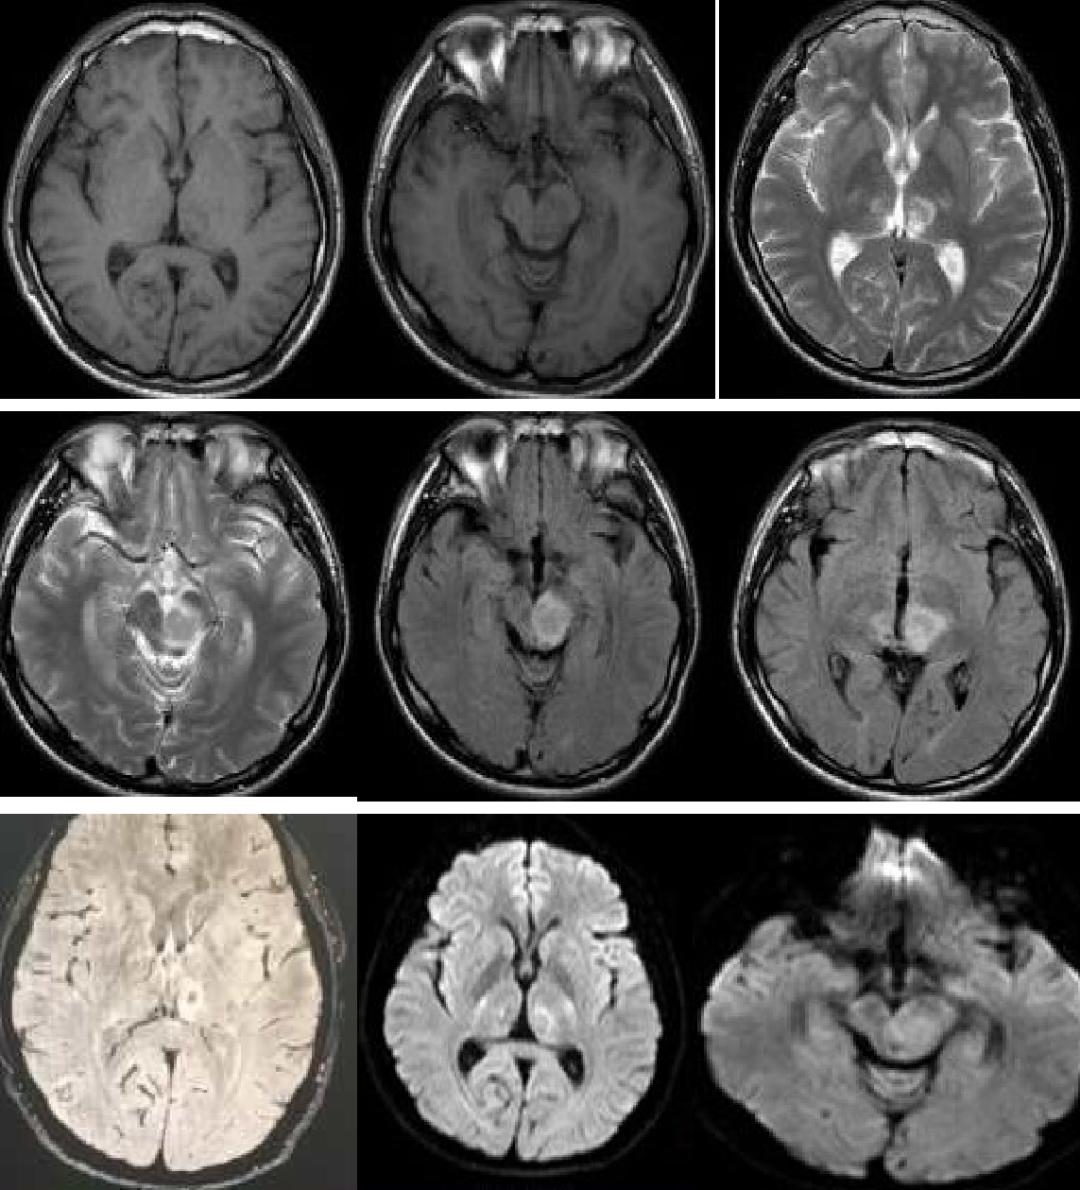

男性50岁,下午睡觉后家属喊不醒,大概4-5小时,之后反应淡漠,右下肢软瘫。

答案:神经梅毒。患者中年男性,急性起病,主要表现为反应迟钝,右下肢软瘫,头颅影像提示以双侧顶枕叶对称性高信号,左侧丘脑点状病灶,额颞叶萎缩。老师们想到了低血糖脑病、PRES、脑梗死、CO中毒等。小僧悟道老师一眼就看出来是梅毒,着实厉害。与年龄不相符的脑萎缩是重要特征。